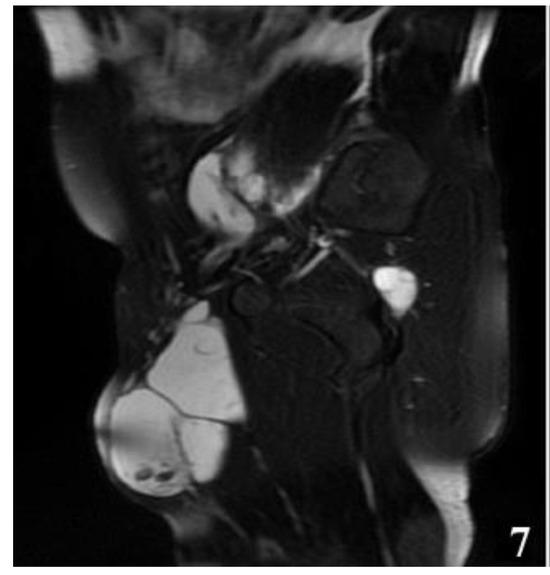

The MRI examination was performed on two patients for surgical purposes, to establish the relationship with other organs or vital structures and to guide the indication and the surgical plan. It is important to note the case of a 32-year-old male patient, hospitalized for the presence of a tumor formation at the base of the left thigh, in which the native and contrast enhanced MRI examination of the pelvis and thigh revealed: urinary bladder without parietal thickenings or endoluminal pathological processes; seminal vesicles without pathological signal changes; prostate measuring 4.7/3.2 cm, homogeneous, without pathological contrast plugs; without suspicious adenomegaly at the pelvic level; replacement process of polylobate space, which is relatively well demarcated, predominantly with fluid signal, multiple septate, without diffusion restriction, with gadophilia present at the peripheral and intralesional septal level, starting from the vicinity of the psoas and iliac muscle on the left side and extending into caudal direction through the anterior portion of the inguinofemoral region on the left side to the proximal region of the left thigh, and coming into contact with the common iliac, external iliac and femoral vessels on the left side (apparently with preserved flow at their level and with the apparently left femoral diaphysis but no macroscopic invasion phenomena at this level); previously described space-replacing process, which extends over a cranio-caudal distance of approximately 33 cm and shows inhomogeneous signal at the level of some of the intralesional cystic areas; deep to the gluteus maximus muscle on the left side, a relatively well-defined area can be seen, with a polylobate contour, multiple septa, with a similar appearance to the previously described space-replacing process, with dimensions of 2.9/2.75 cm—possibly parasitic cystic lesions (Figure 4, Figure 5, Figure 6, Figure 7, Figure 8 and Figure 9).

Figure 7.

T2W MRI sequence, sagittal—Hydatid cyst left iliopsoas muscle and left thigh (part 1).